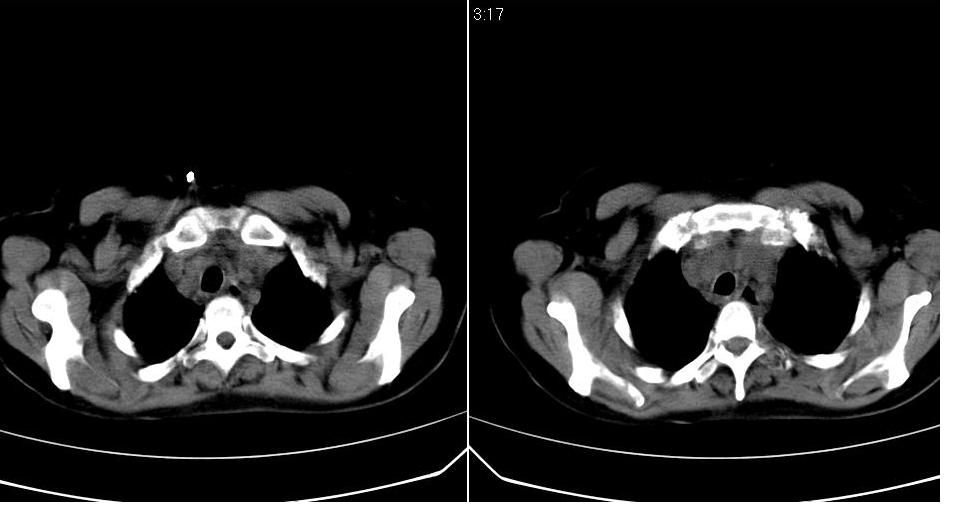

标题: CT16839:胸部CT平扫

女 50岁,在其他医院确诊肺癌.

支持 右肺上叶肺癌并两肺及纵隔转移。

肺癌并肺内及纵隔淋巴结转移